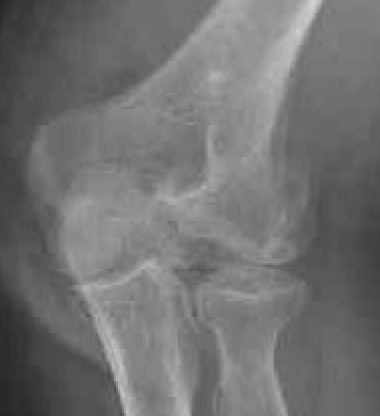

Double arc sign seen on xray

Double arc sign on xray

Dubberly Classification

Type I Type Ii Type III

Capitellum + trochlea fracture

In one piece